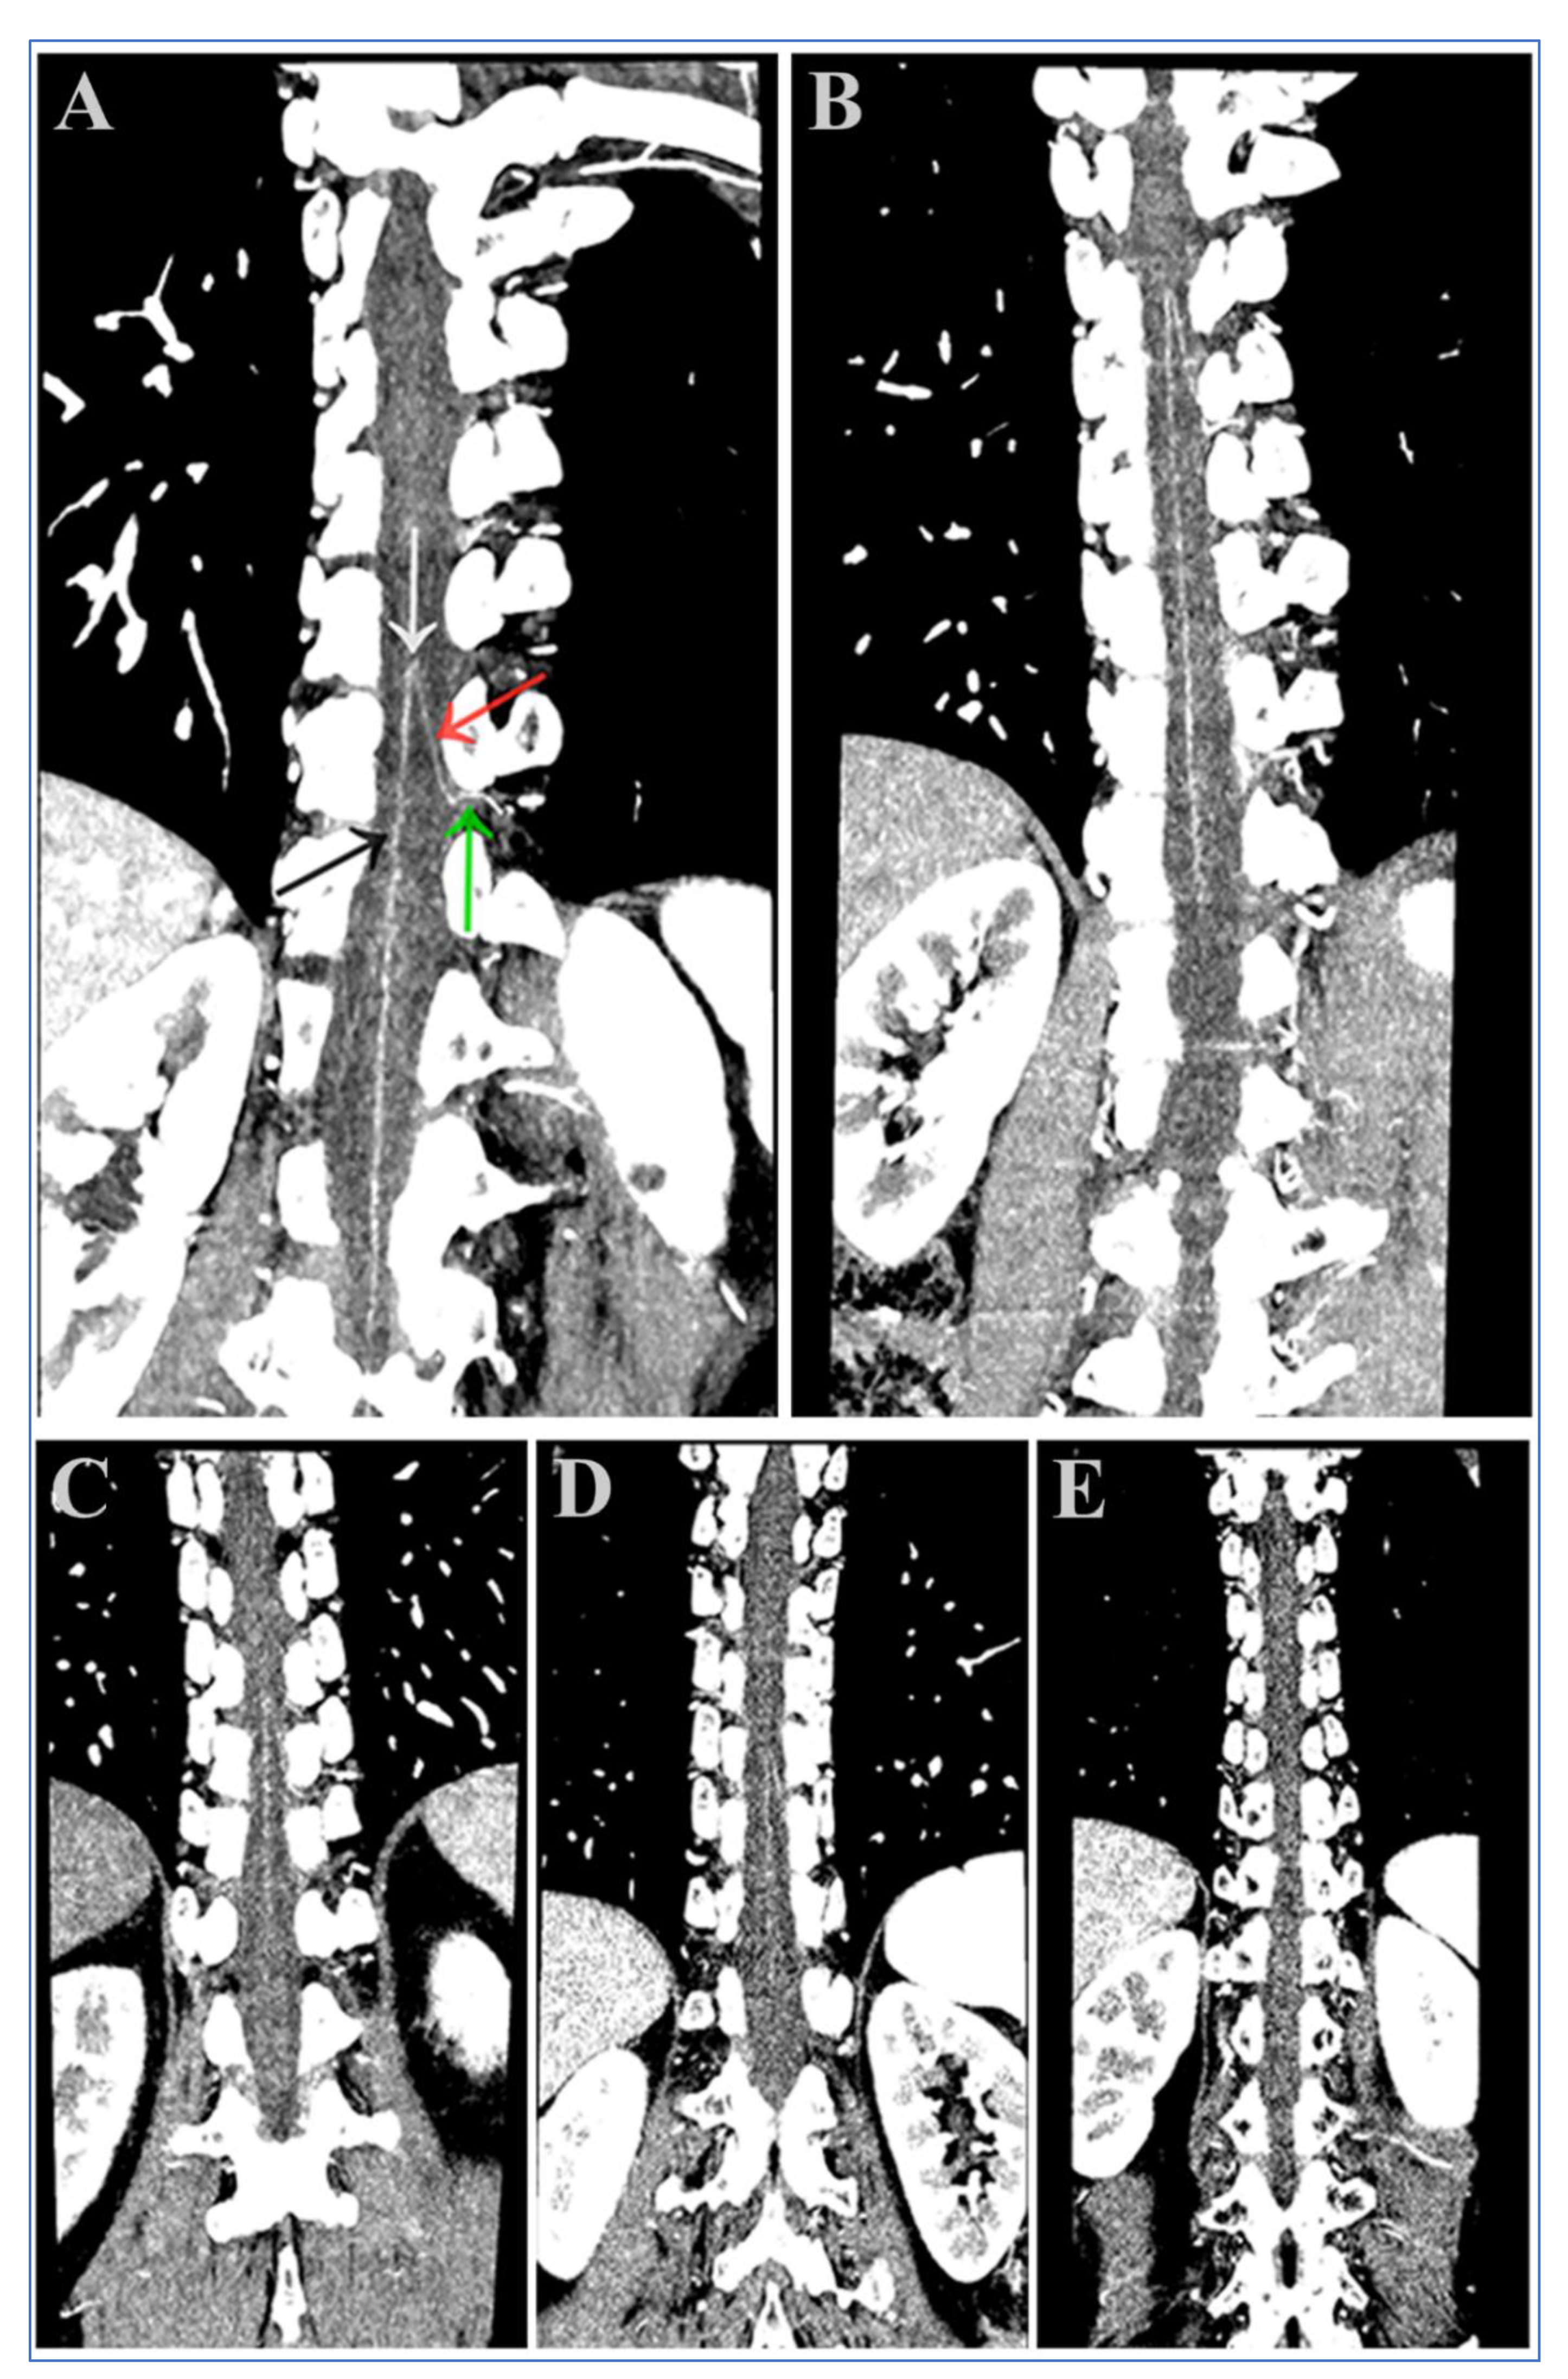

2.6. Visual Assessment of the AKA

3.4. Visual Analysis of the AKA